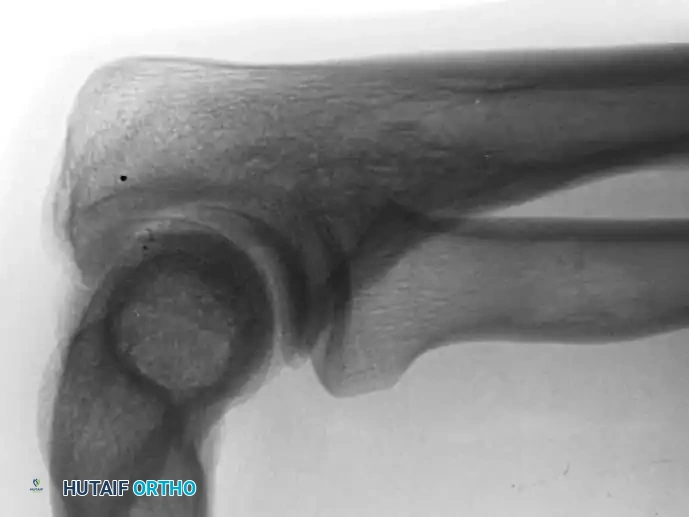

Distal Humerus and Elbow Reconstruction

When tumors involve the distal humerus, resection often requires sacrifice of the collateral ligaments and the articular surface of the elbow. Reconstruction is typically achieved using a linked, semi-constrained total elbow arthroplasty designed for oncologic defects.